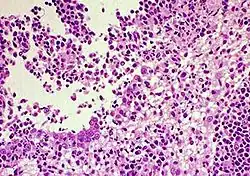

| FIP-infected kidney showing inflammatory response | |